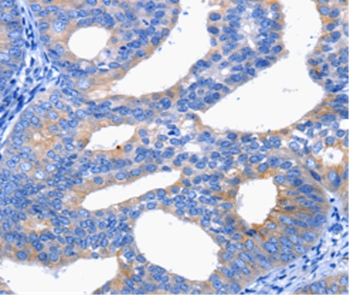

Immunohistochemical analysis of paraffin-embedded Human cervical cancer tissue using #36808 at dilution 1/25.